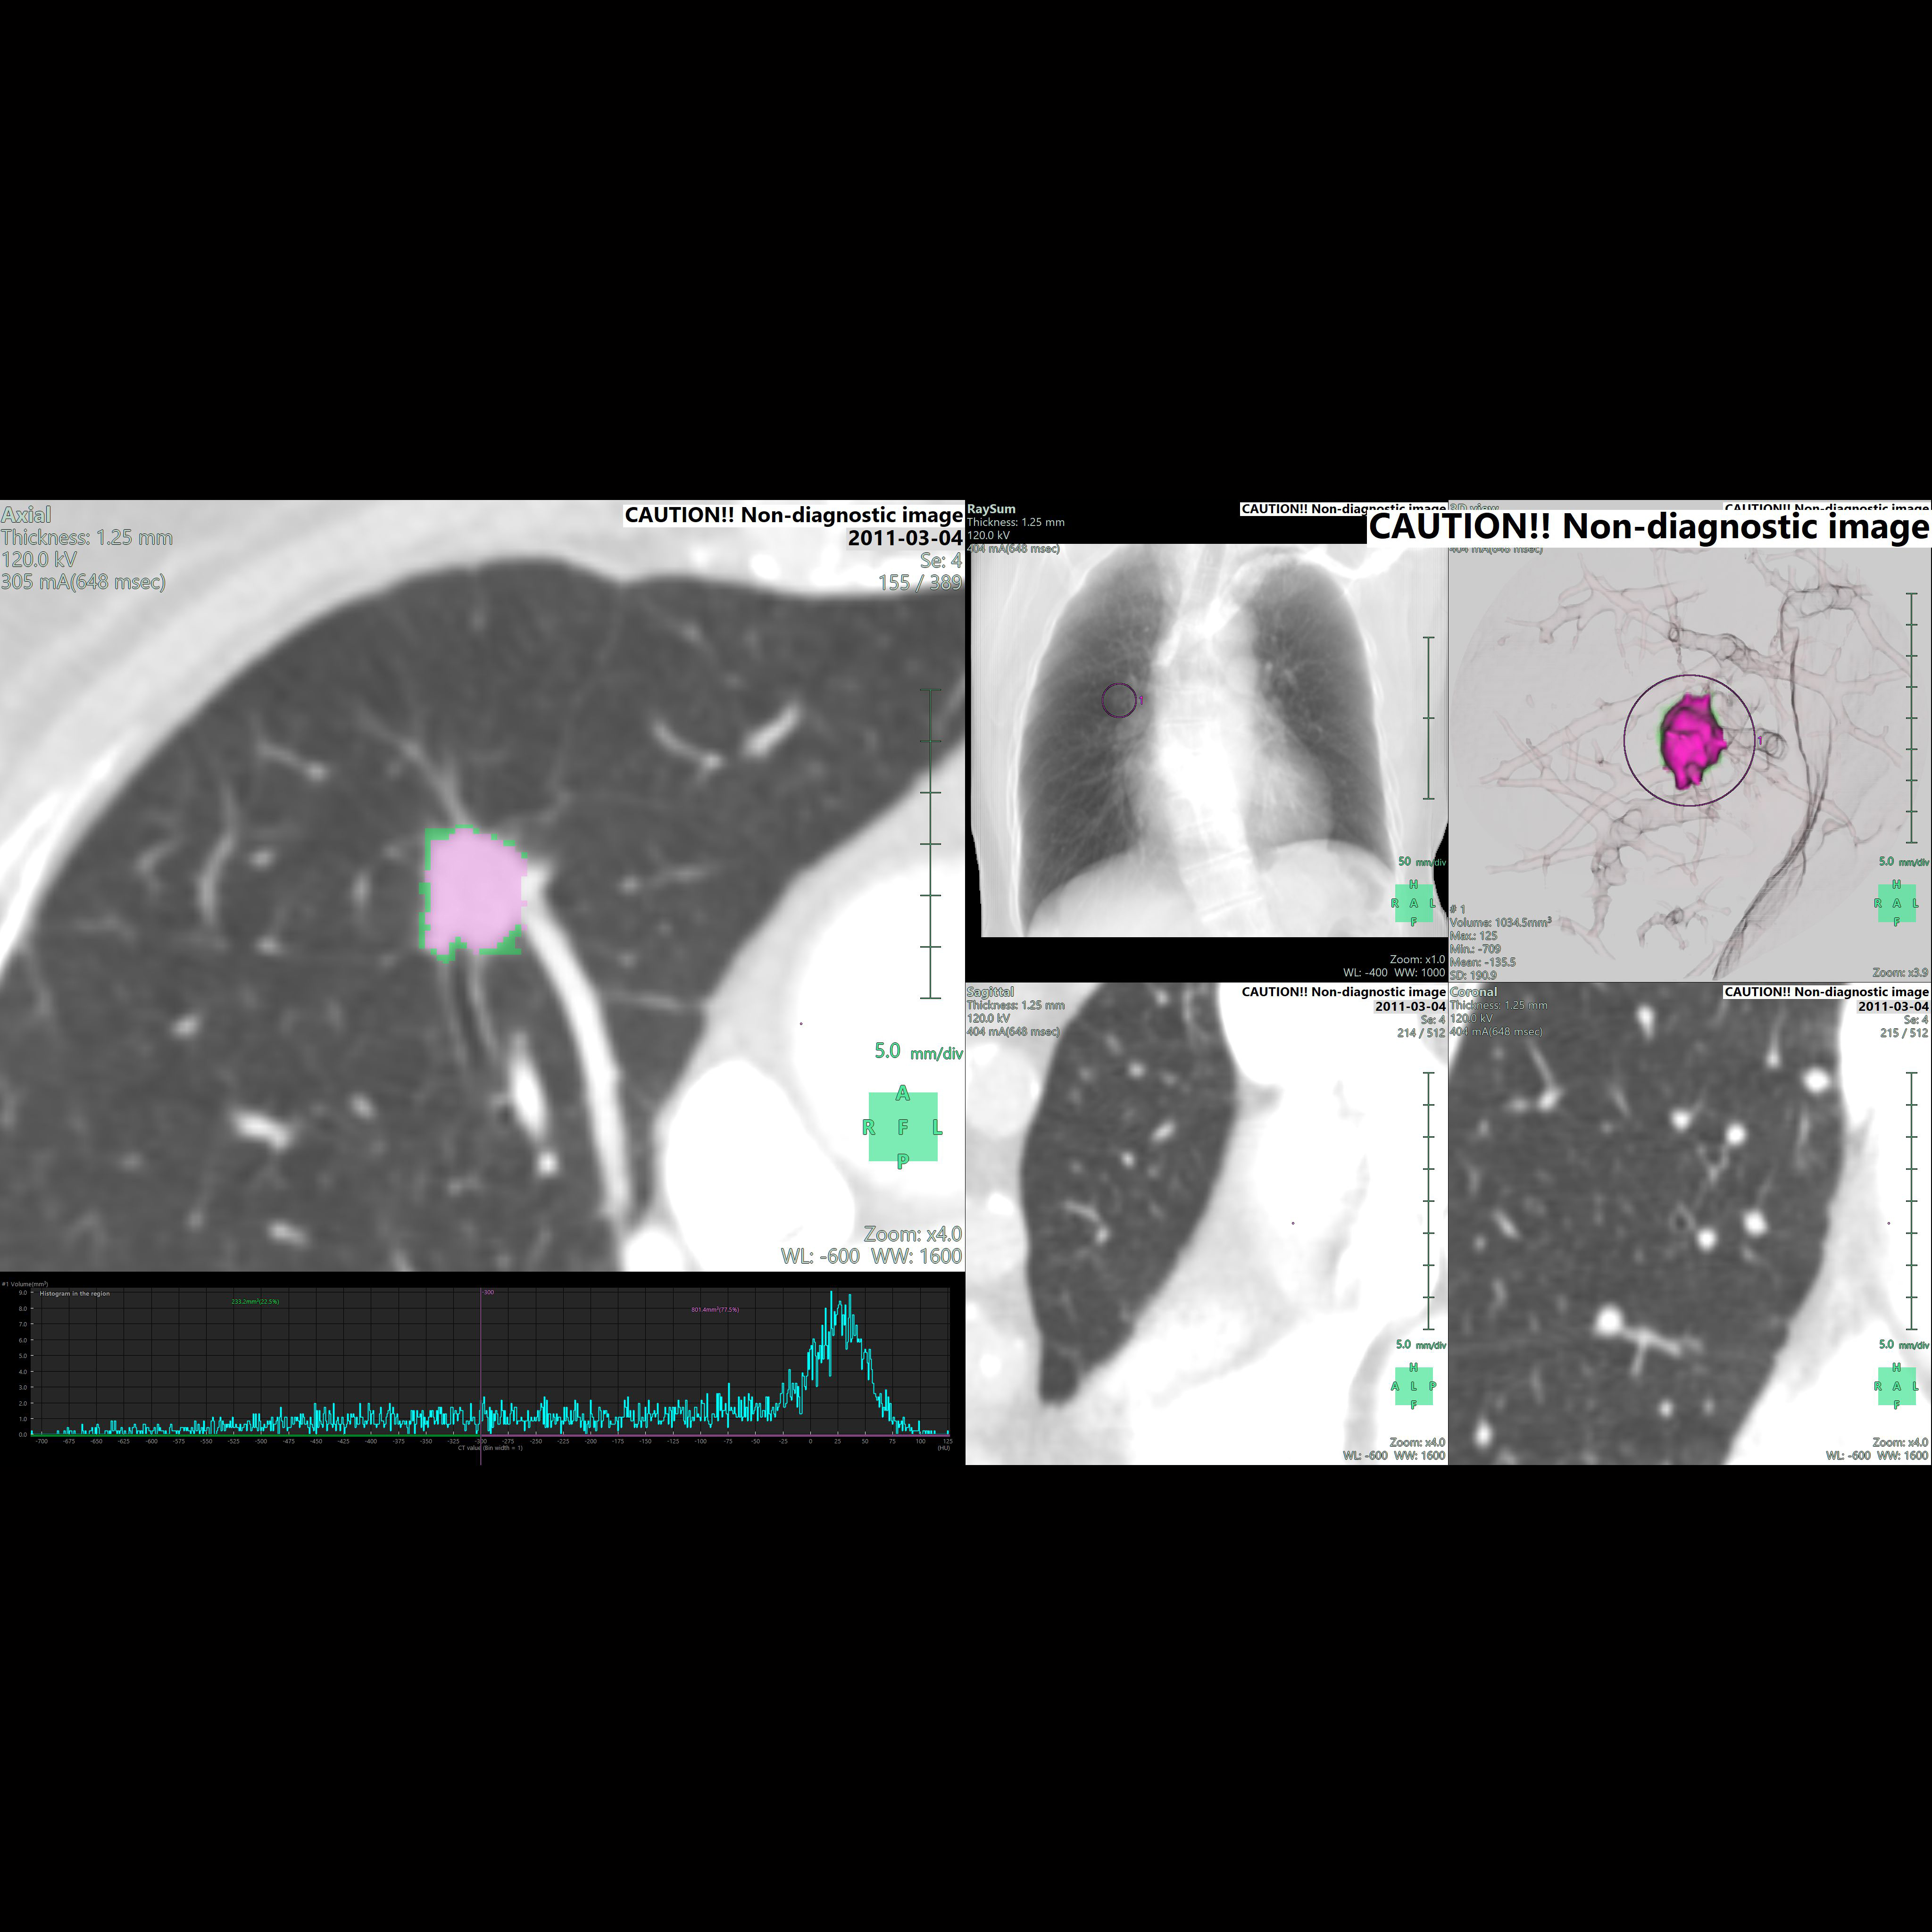

• - CT image를 사용하여 nodule까지의 path를 구성하고 관찰할 수 있습니다.

• - Bronchus의 직경 End-point부터 Nodule 까지의 거리 등을 확인하며 가상 내시경을 진행할 수 있습니다.

Axial view